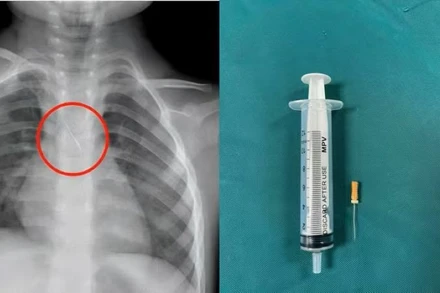

Ngày 21/1, Bệnh viện hữu nghị Việt Nam–Cuba Đồng Hới, tỉnh Quảng Trị cho biết, vừa phẫu thuật cấp cứu thành công 1 trường hợp thanh niên bị đinh từ súng bắn đinh xuyên thành bụng, thủng ruột non trong lúc lao động.